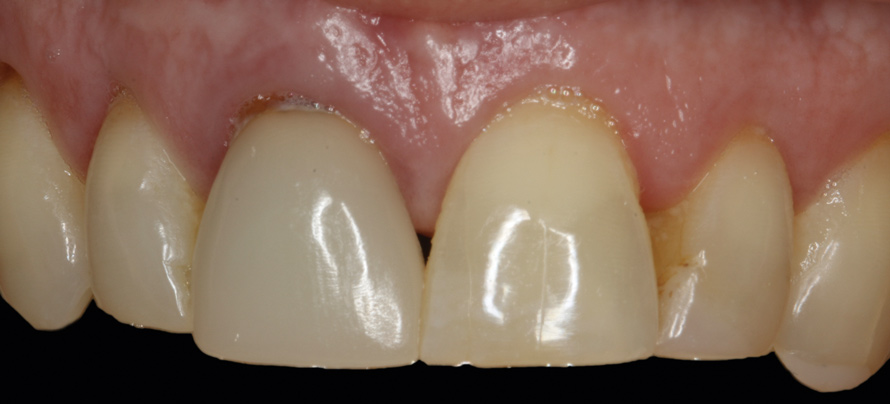

4. Facial and occlusal views of initial clinical presentation of tooth No. 8.

Figure 4

5. Facial and occlusal views of initial clinical presentation of tooth No. 8.

Figure 5